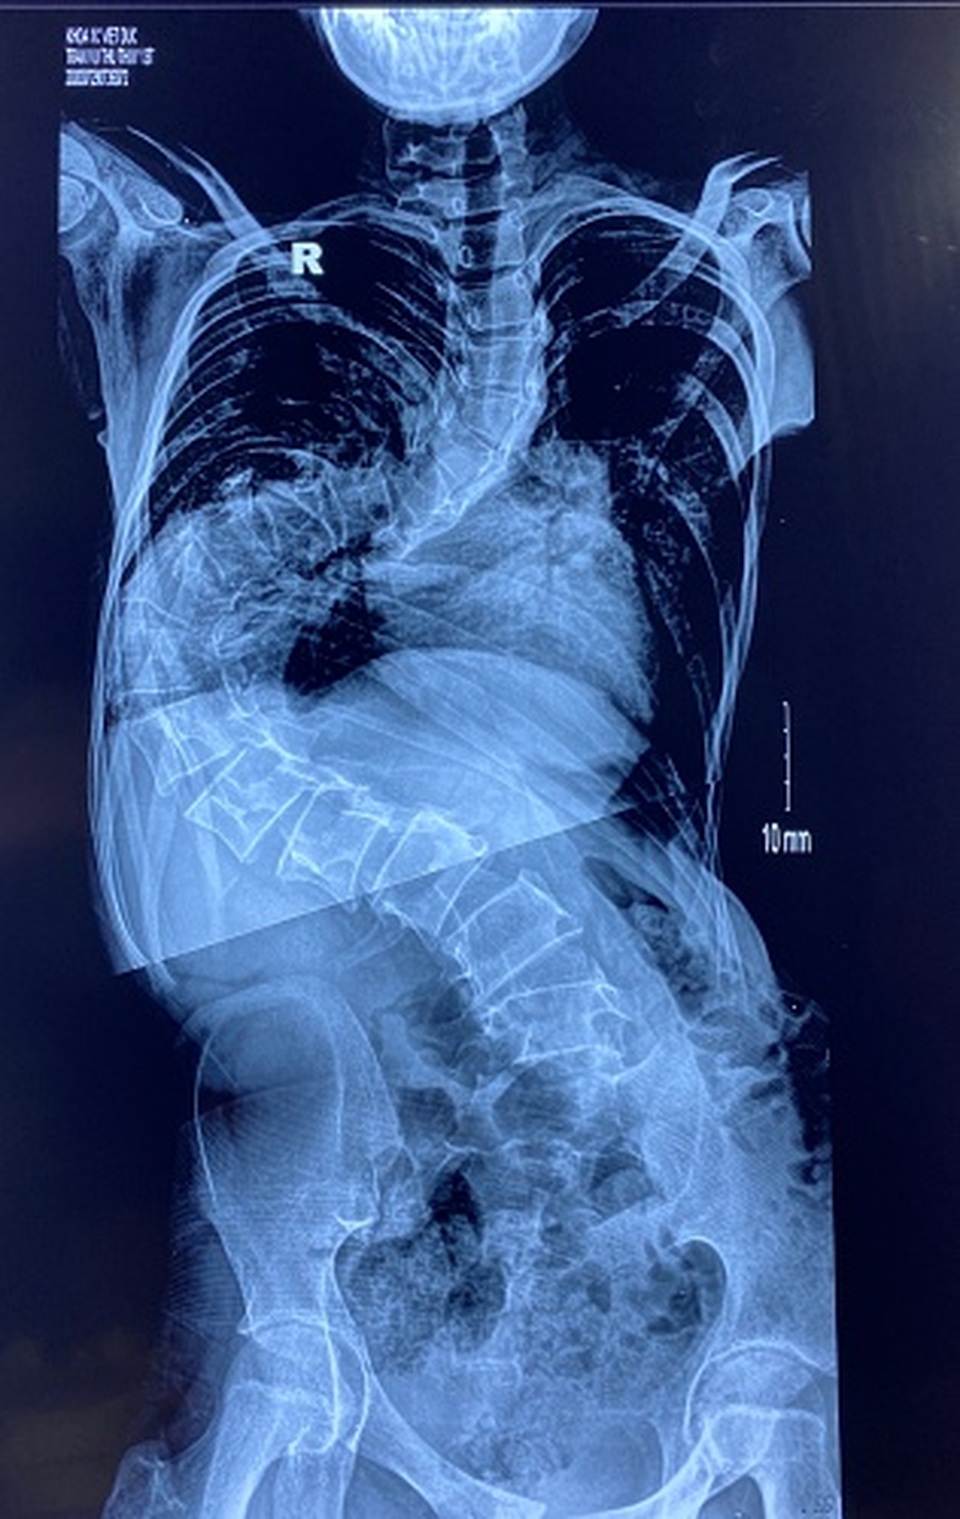

Mới đây, khoa Phẫu thuật Cột sống, Bệnh viện Việt Đức (Hà Nội) tiếp nhận một bé gái 13 tuổi, ở Hà Nội bị vẹo cột sống một góc 150 độ. Hình ảnh trên phim chụp cho thấy cột sống bệnh nhân uốn lượn như hình chữ S. Các đốt sống bình thường xếp chồng lên nhau thành một đường thẳng đứng thì nay xếp thành đường cong. Đốt sống nằm sát vào thành ngực thay vì nằm giữa cơ thể.

TS.BS Nguyễn Hoàng Long, Phó khoa Phẫu thuật Cột sống cho biết một trường hợp được chẩn đoán bị gù vẹo cột sống khi góc vẹo từ 10 độ trở lên, góc vẹo từ 100 độ trở lên như trường hợp này là rất nặng, ảnh hưởng đến chức năng tim phổi. Nguyên nhân của trường hợp này là do trẻ mắc hội chứng Marfan, độ vẹo tăng dần theo thời gian.

Theo lời của gia đình, trẻ đã được điều trị ở nhiều nơi, có mặc áo chỉnh hình nhưng góc vẹo tiến triển lên, cột sống uốn cong theo hình chữ S.